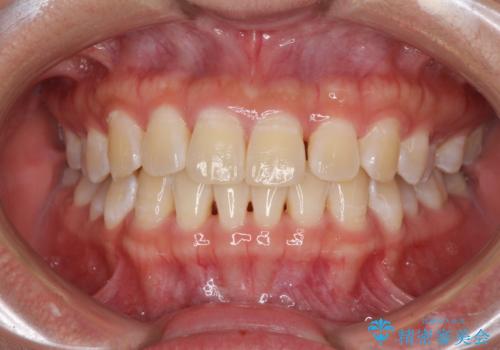

前歯の隙間と上下正中のズレを解消

- 上下前歯隙間と正中のズレを改善したいとのことで来院された患者様です。

自己管理を減らしたいとのことで、ワイヤー装置による矯正治療を行うこととしました。

正中がなかなか合わずに、2年近くの治療期間を要しました。